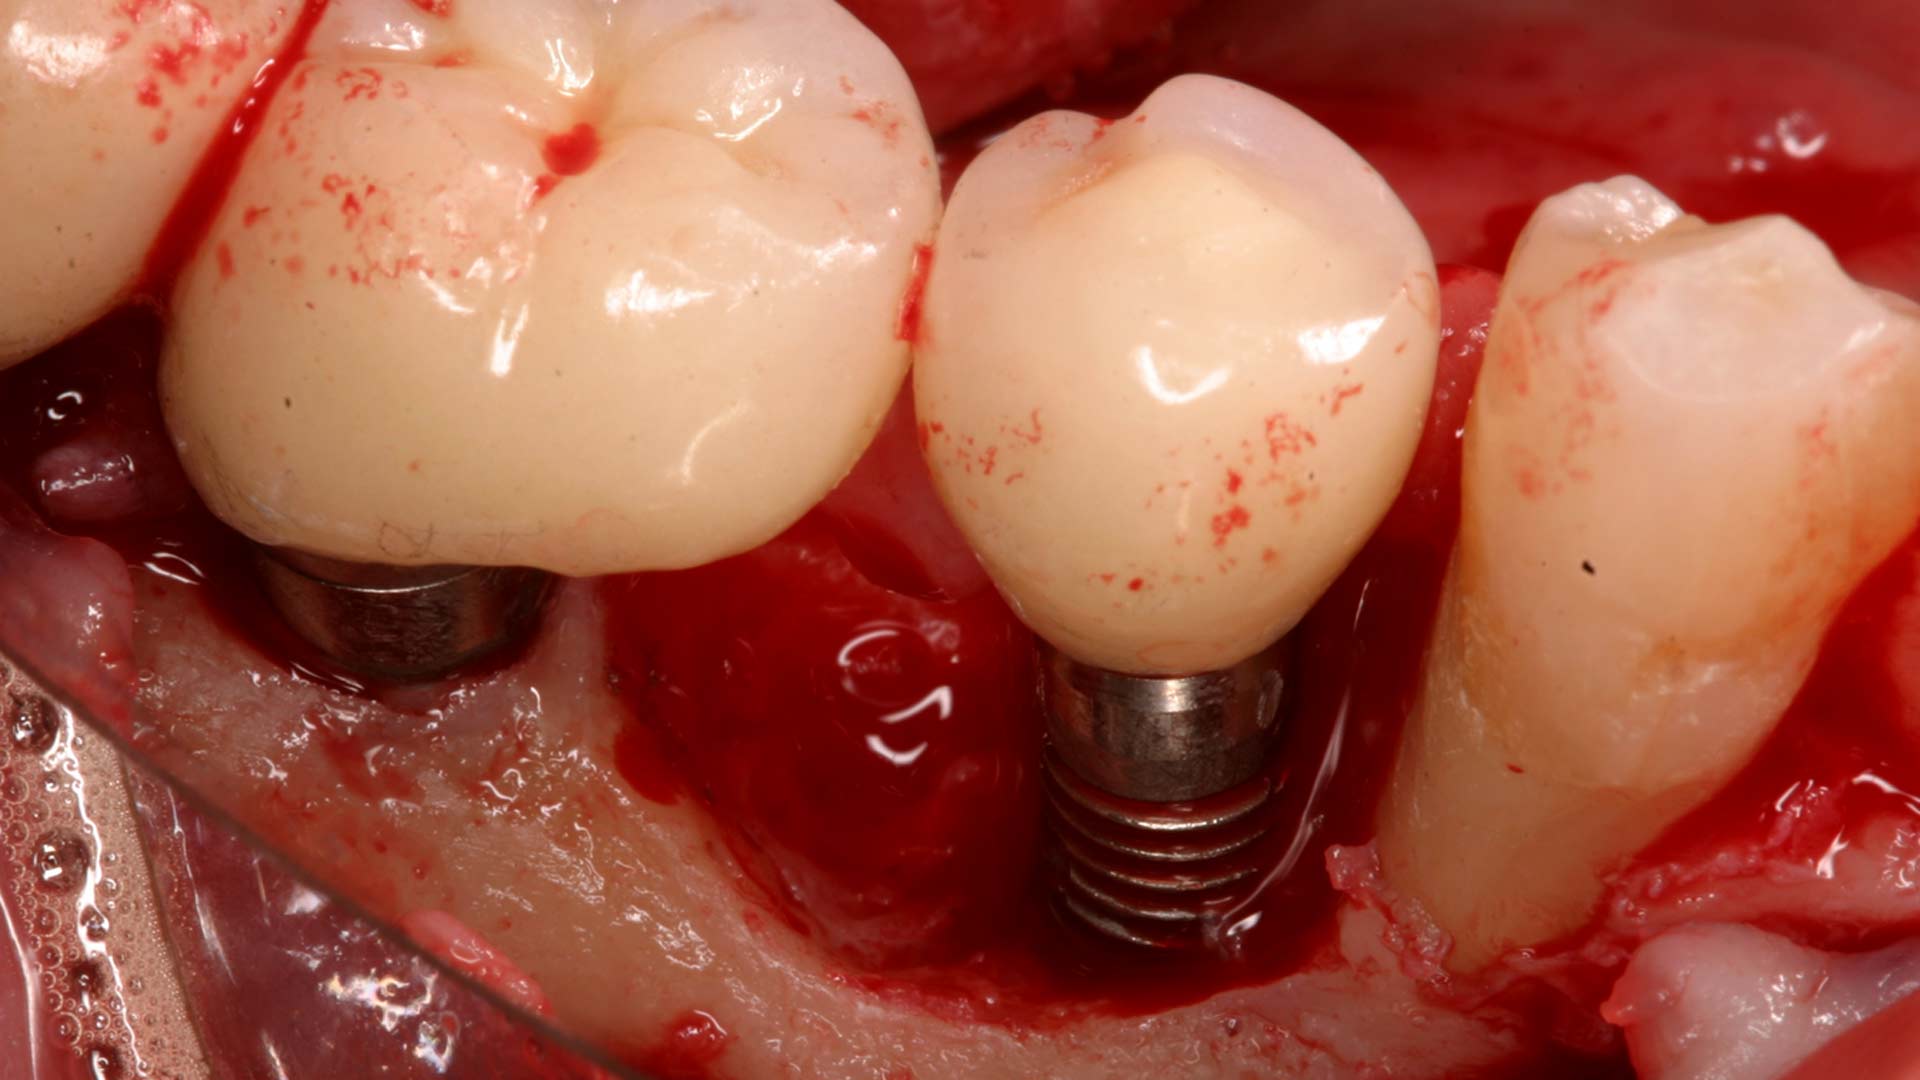

Dental implants are permanently situated in your mouth, so unlike dentures, they stay in place just like your own teeth. The root of the tooth is replaced by a screw, which becomes the artificial root. The screw sits in the jawbone and fuses with your jawbone, helped by the bone graft procedure.

The bottom line is these factors all influence how your body heals. Receiving dental implants first relies on your body integrating your bone grafts, and then on your jaw being strong enough to support the titanium implant screw for each implant.

It is also imperative that your gums heal well, as weakness in the seal around your new implant can lead to infection. This is why gingivitis is a risk factor. It is also partly why grinding can be a problem, as the teeth need to be still for your mouth to heal fully.

Another reason that tooth grinding hinders success is that movement slows down the osseointegration. This is the process of the bone fusing with the implant and forming a permanent attachment.

A worst-case scenario would be an infection taking hold in your jawbone post-surgery. In the very worst of circumstances, it could lead to the implants not taking well and possibly needing to be removed for the infection to heal.

Signs of dental implant infection

Typical signs of dental implant infections are:

- Pain around the area or in the jaw

- High temperature or fever

- Feeling that the implant has loosened

- Swelling, bleeding or redness in the gums

- Pain or difficulty when chewing

- Pus or other fluid coming from the implant site or surrounding gums

- Bad smelling breath

- An unpleasant taste in your mouth that won’t go away